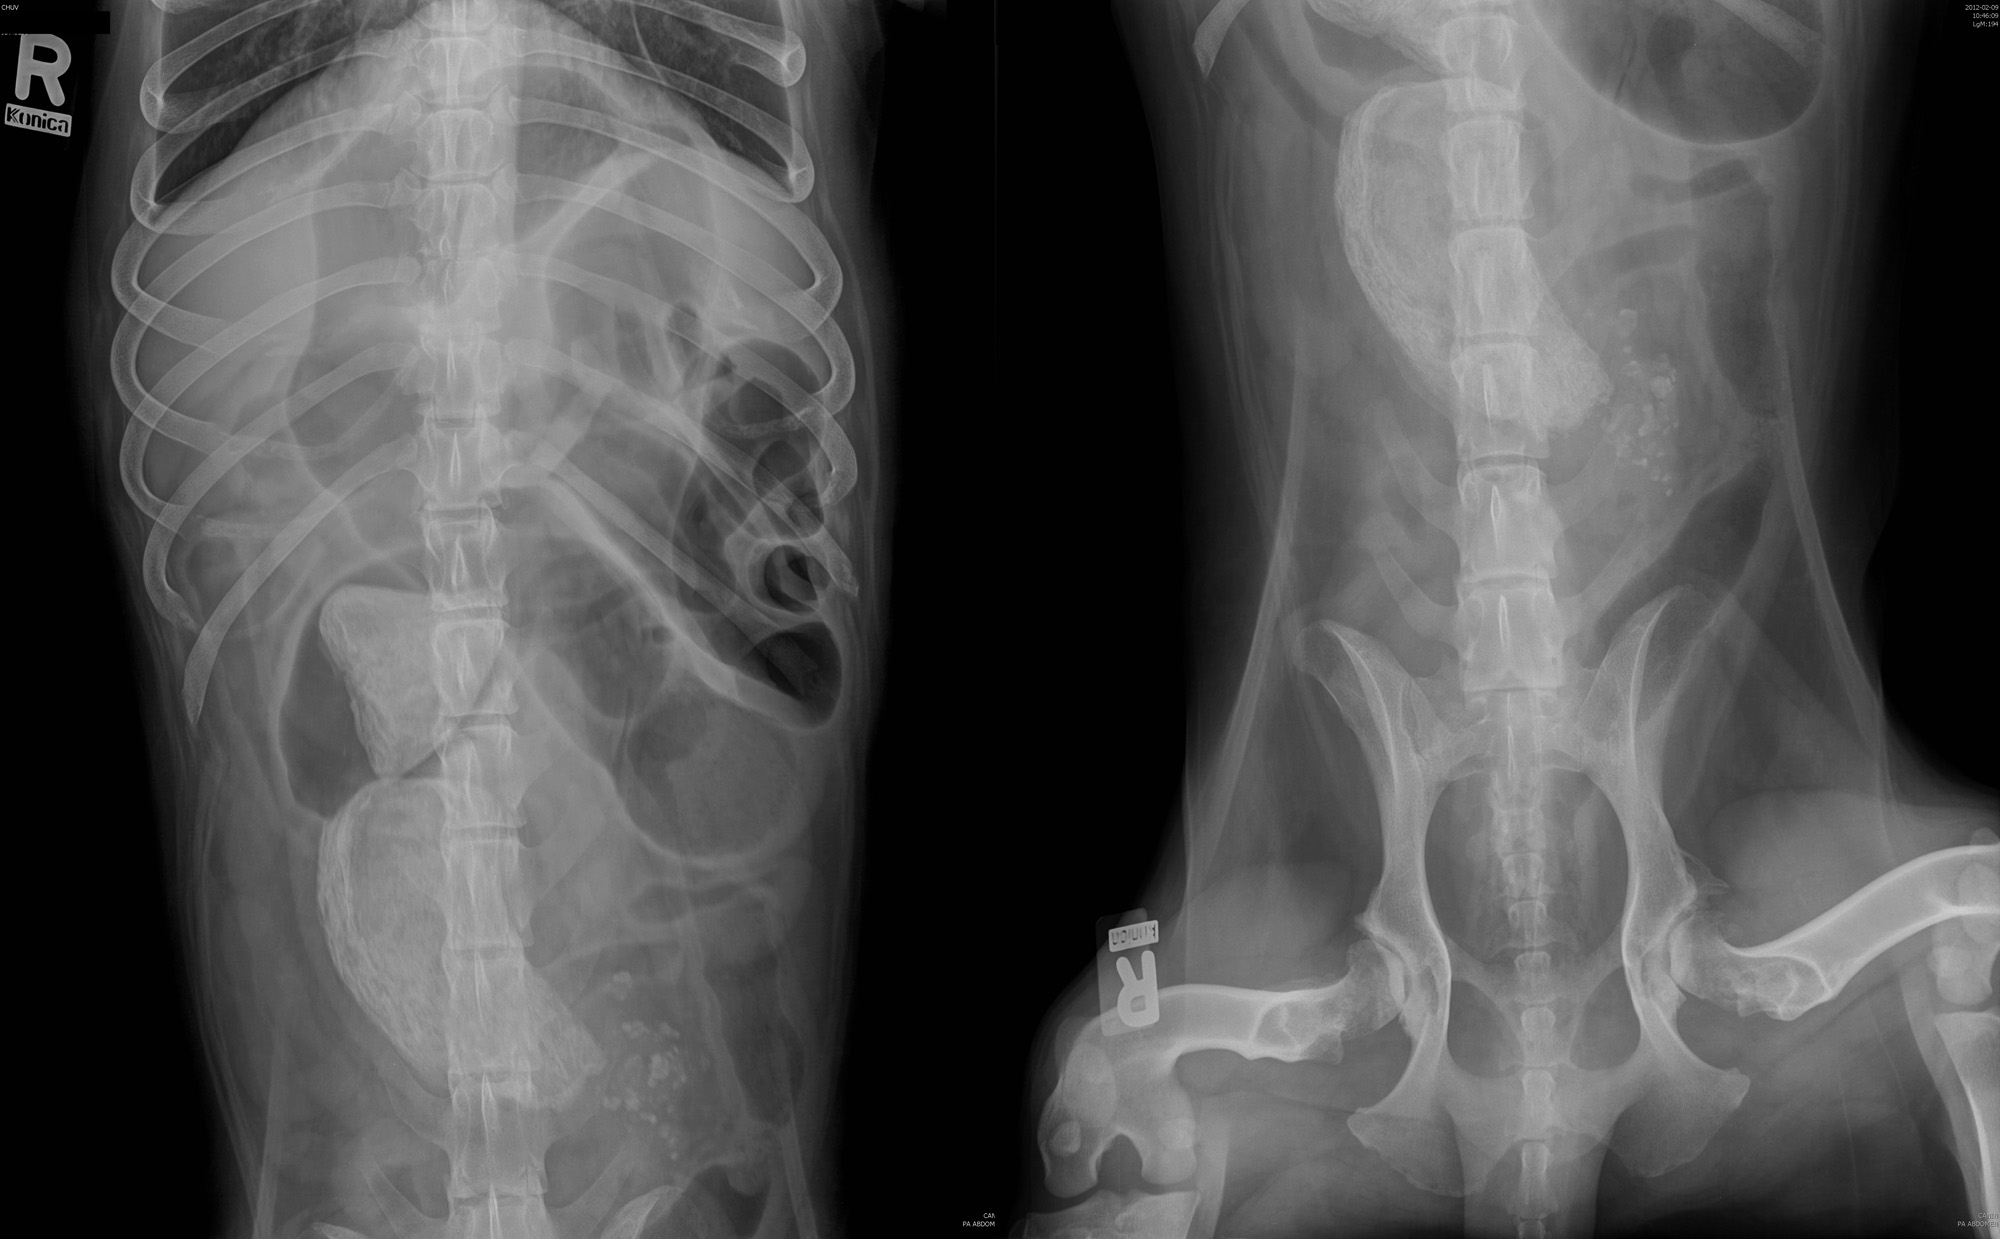

Signalement: Labrador de 5 ans, mâle castré.

Histoire clinique: Amaigrissement progressif depuis 3 mois, avec courts épisodes de selles liquide, mais sans vomissement. Hypoprotéinémie.